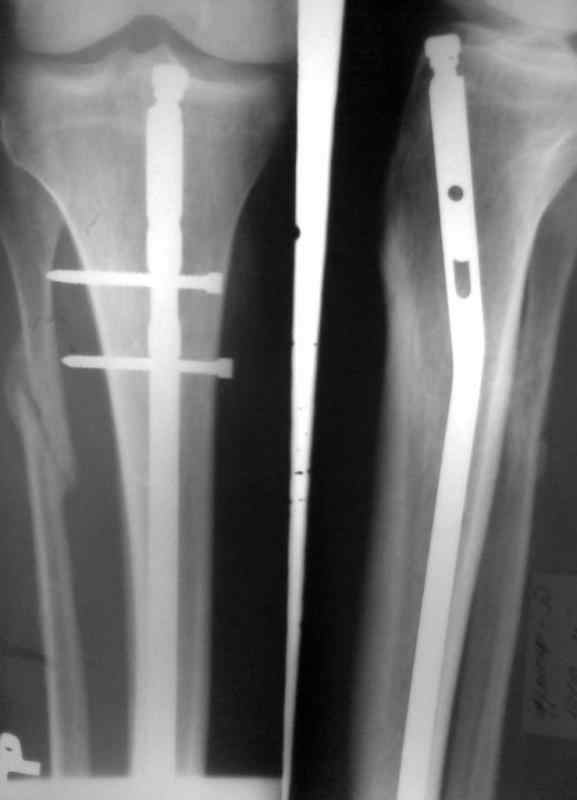

Сломан дистальный блокирующий винт Больному произведено ОМС перелома голени блокирующим стежнем 2 мес. назад. Через 1 мес больной начал наступать на ногу. В результате такая картина. Удален сломаный конец винта.Интересует вопрос о дальнейшей тактике лечения. Кто может посоветовать как дальше поступить. Оставить все как есть и приступать на ногу, провести замену стержня на другой или поступить как-то иначе. Спасибо за советы и предложения

снимки в приложении

Я за этот вариант.. Заменить на более длинный!!! и большего диаметра!!!, с предварительным рассверливанием!!! и блокированием дистально не одним 4,5 мм винтом!!!, а минимум двумя, или еще лучше тремя 5,0 или винтами... Проксимально можно ограничится динамическим блокированием

Мое мнение - есть хорошая мозоль, и ось конечности весьма неплоха. Я бы оставил все как есть и рекомендовал бы больному на всякий случай повременить с нагрузкой на ногу еще на пару месяцев .

Конечно, изначально было бы лучше гвоздь взять на 2-4 см длиннее ( скорее на 4) и заблокировать его 2-3 шурупами, но, что сделано - то сделано